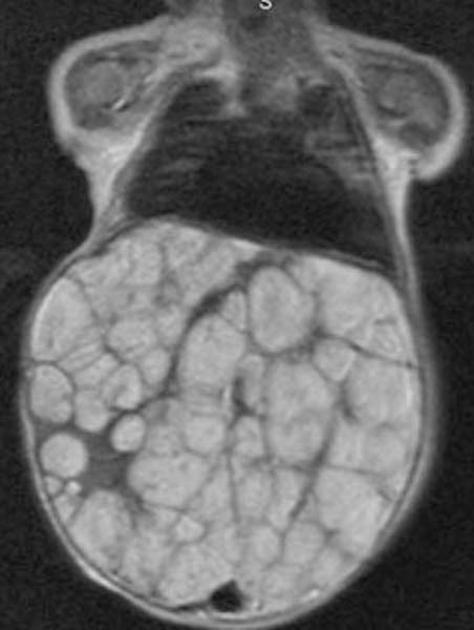

Nephroblastomatosis

multifocal/diffuse nephrogenic rests–> persistence of metanephric blastema

precursor to wilms

Associated with: BW, WAGR, and hemihypertrophy